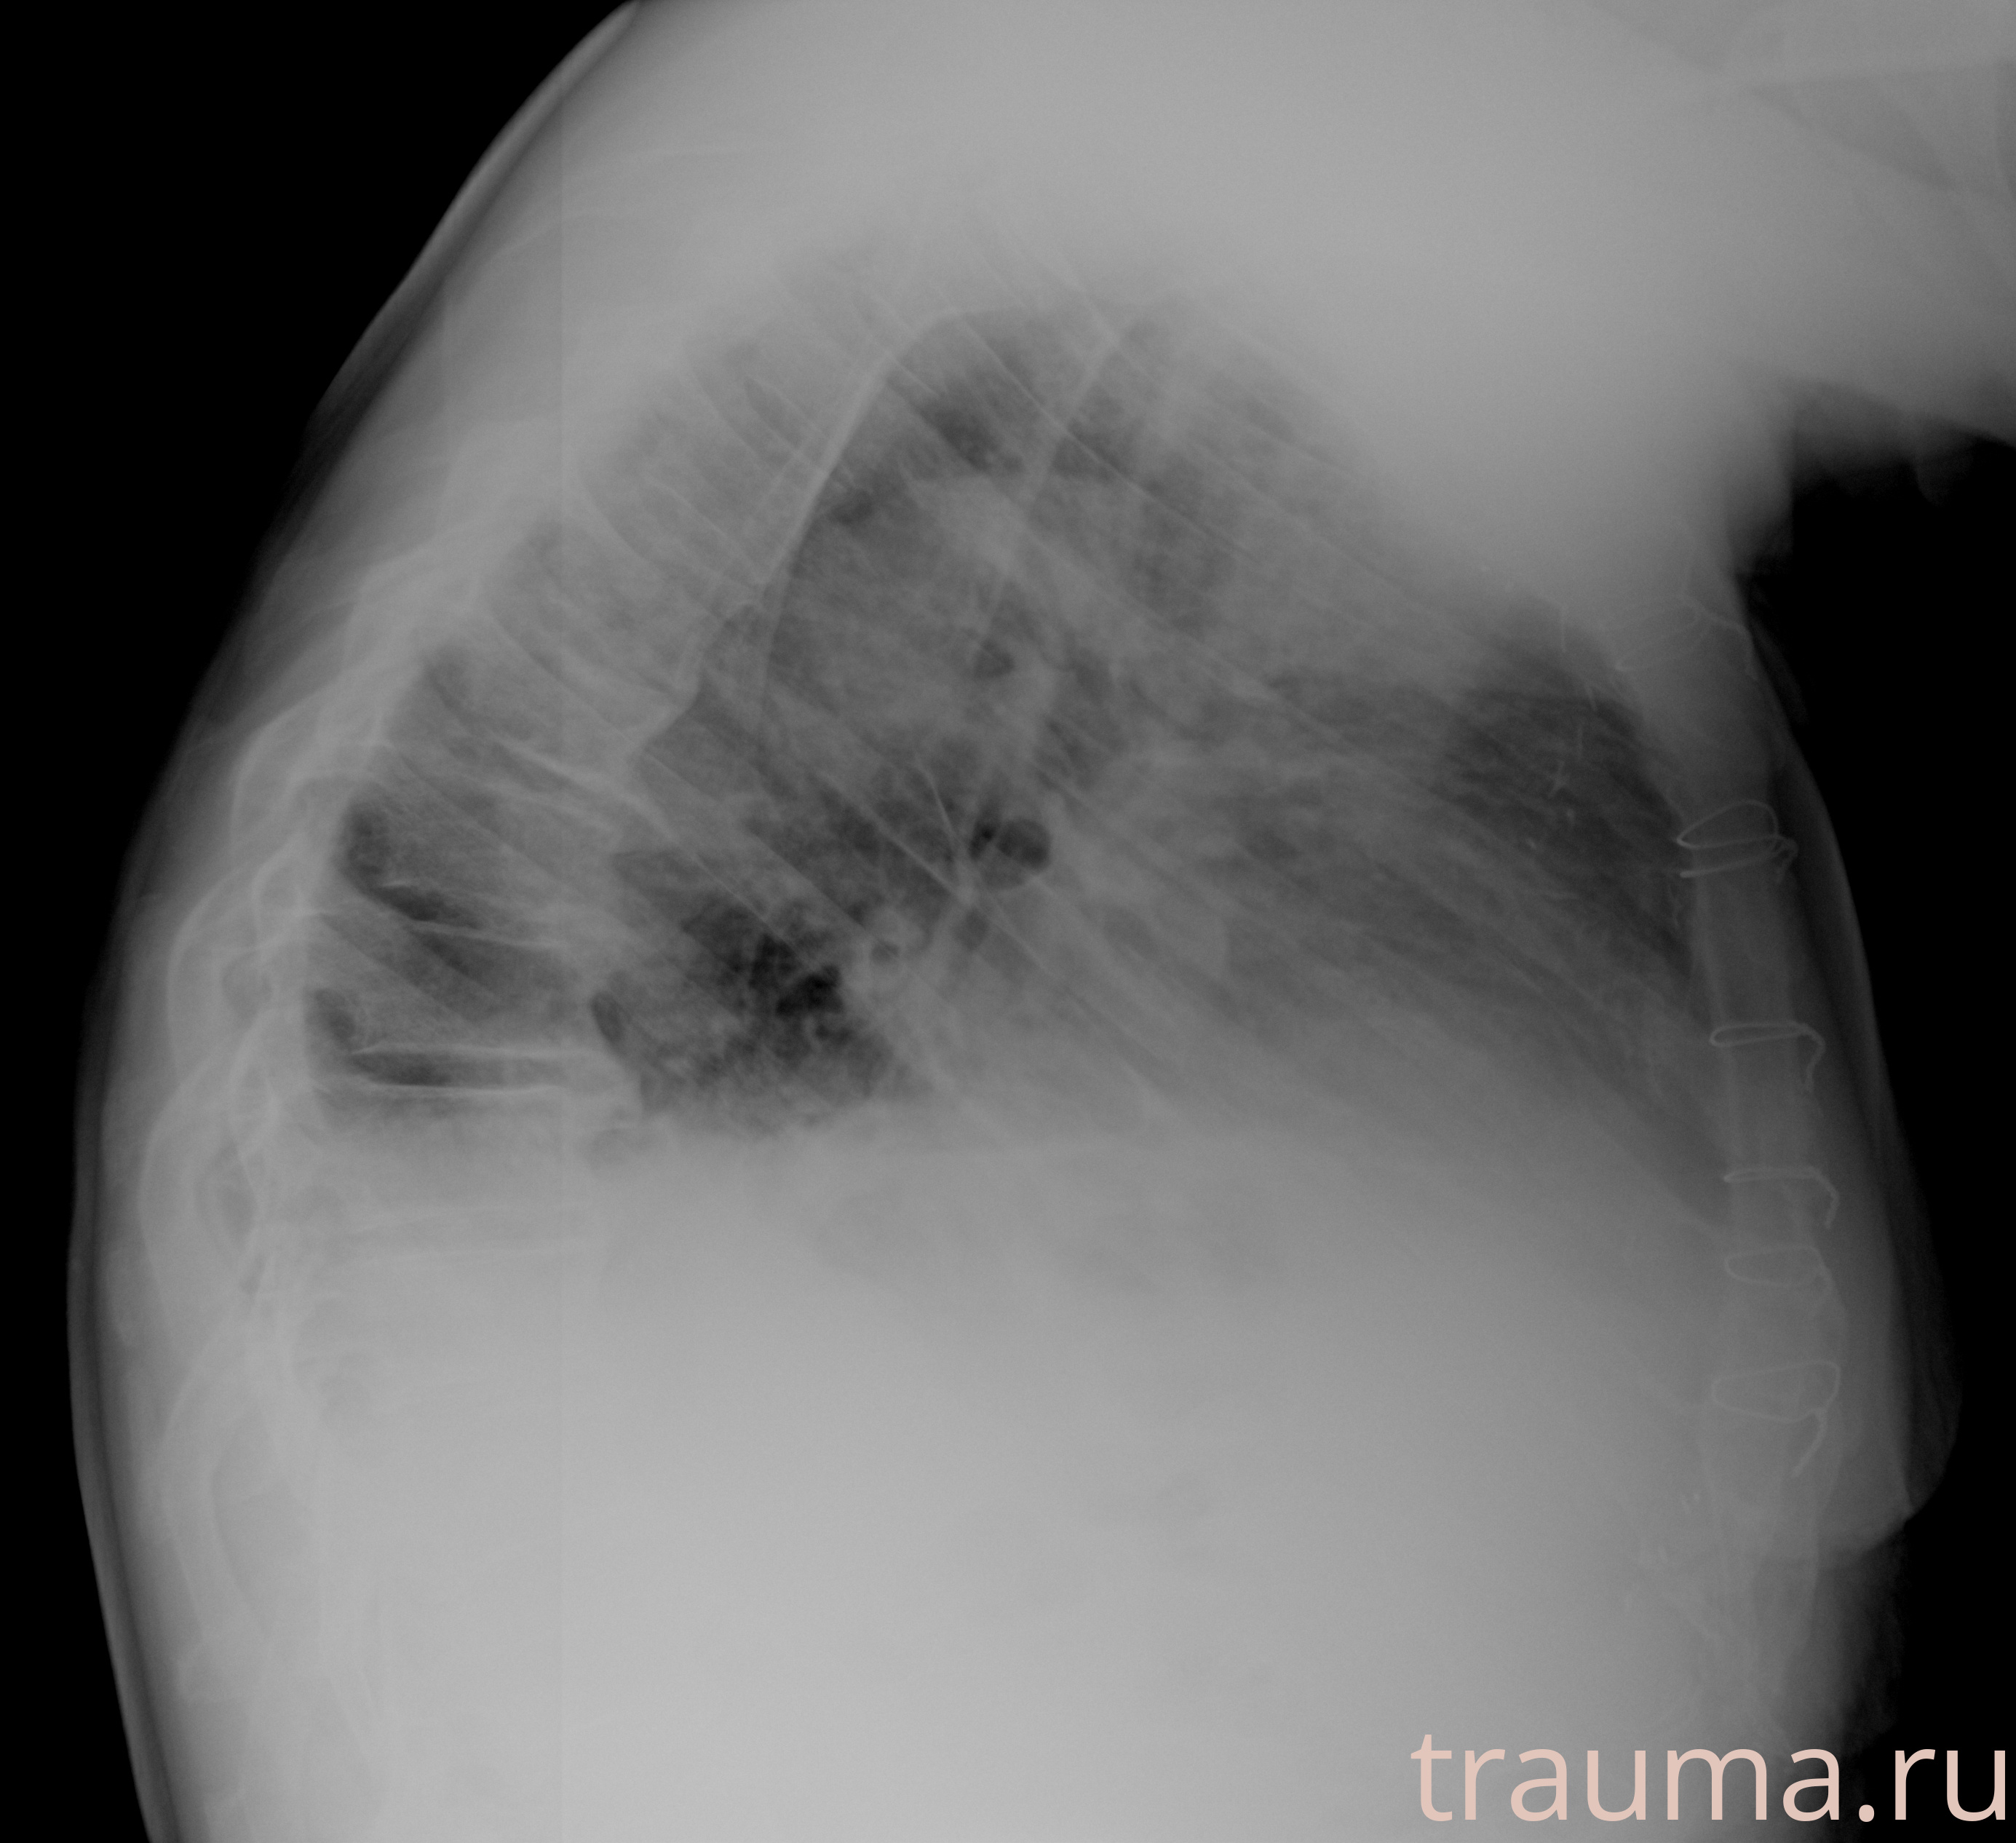

Рентген на дому: по вашему адресу приезжает врач-рентгенолог, травматолог-ортопед с мобильным рентгеновским аппаратом, проводит диагностику травмы или заболевания, делает необходимые рентгенограммы, дает рекомендации по дальнейшему лечению. Получить качественные снимки в домашних условиях возможно благодаря уникальной методике, разработанной МосРентген Центром для института  Склифосовского

при переломе шейки бедра и пневмонии от компании МосРентген Центр - партнера Института имени Склифосовского